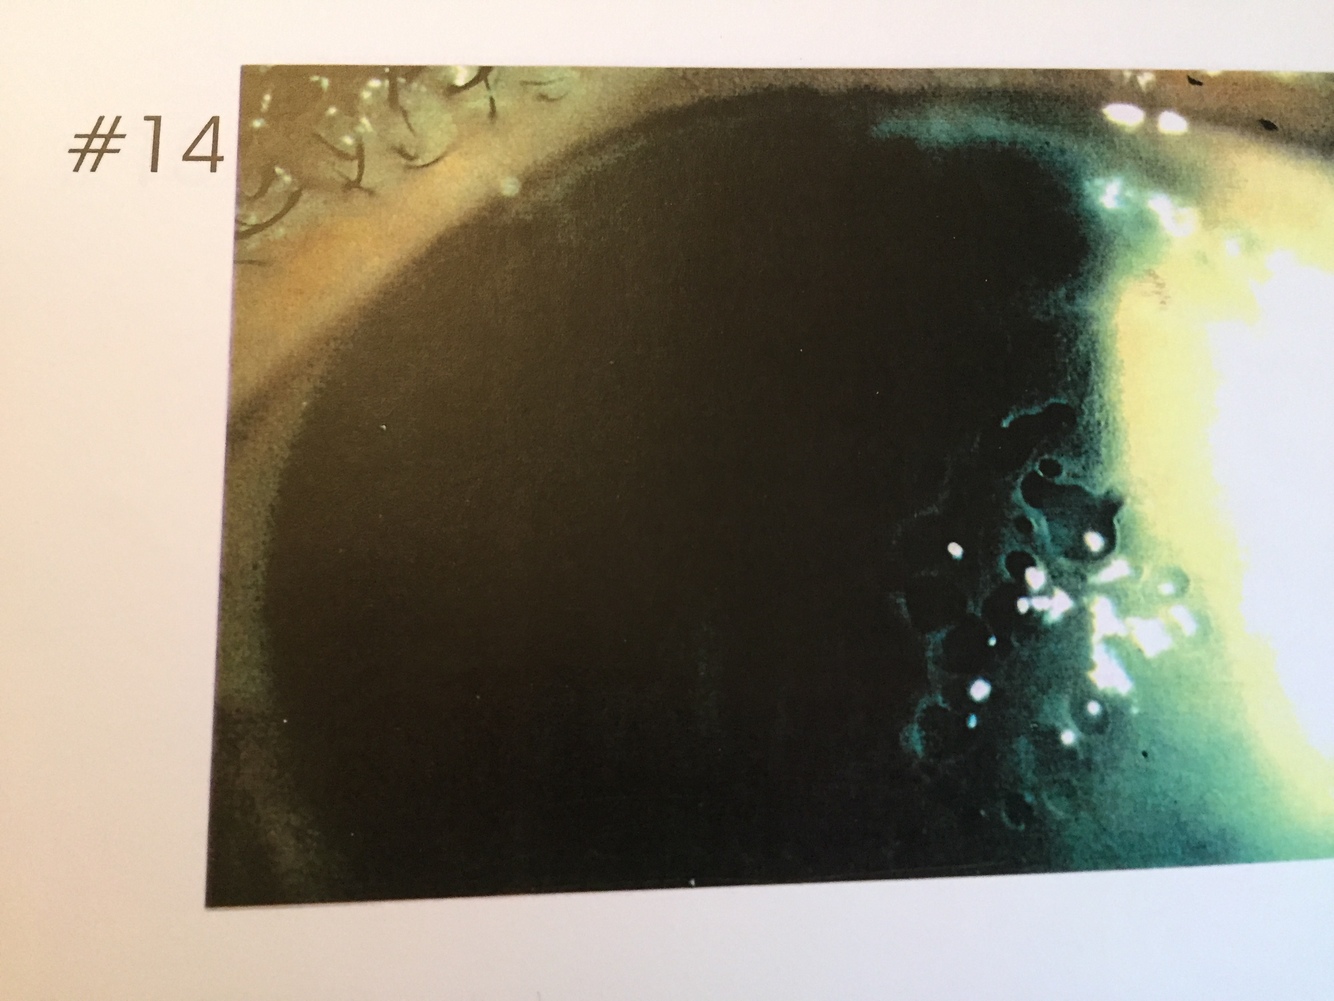

14.

Bulbous Keratopathy

Refer ASAP

Bullous keratopathy is most common in older people and occurs after surgery, such as cataract removal. The swelling leads to the formation of fluid-filled blisters on the corneal epithelium. A condition that often concurs with bullous keratopathy is stromal edema, which is caused by a compromise in the endothelial cell pump mechanism. Vision loss can be mild to severe and pain is associated with the blisters on the surface of the cornea.